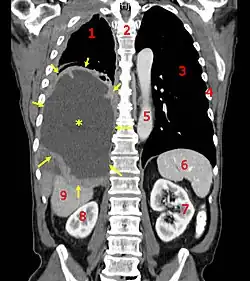

| A coronal CT scan showing a malignant mesothelioma Legend: → tumor ←, ✱ central pleural effusion, 1 & 3 lungs, 2 spine, 4 ribs, 5 aorta, 6 spleen, 7 & 8 kidneys, 9 liver | |